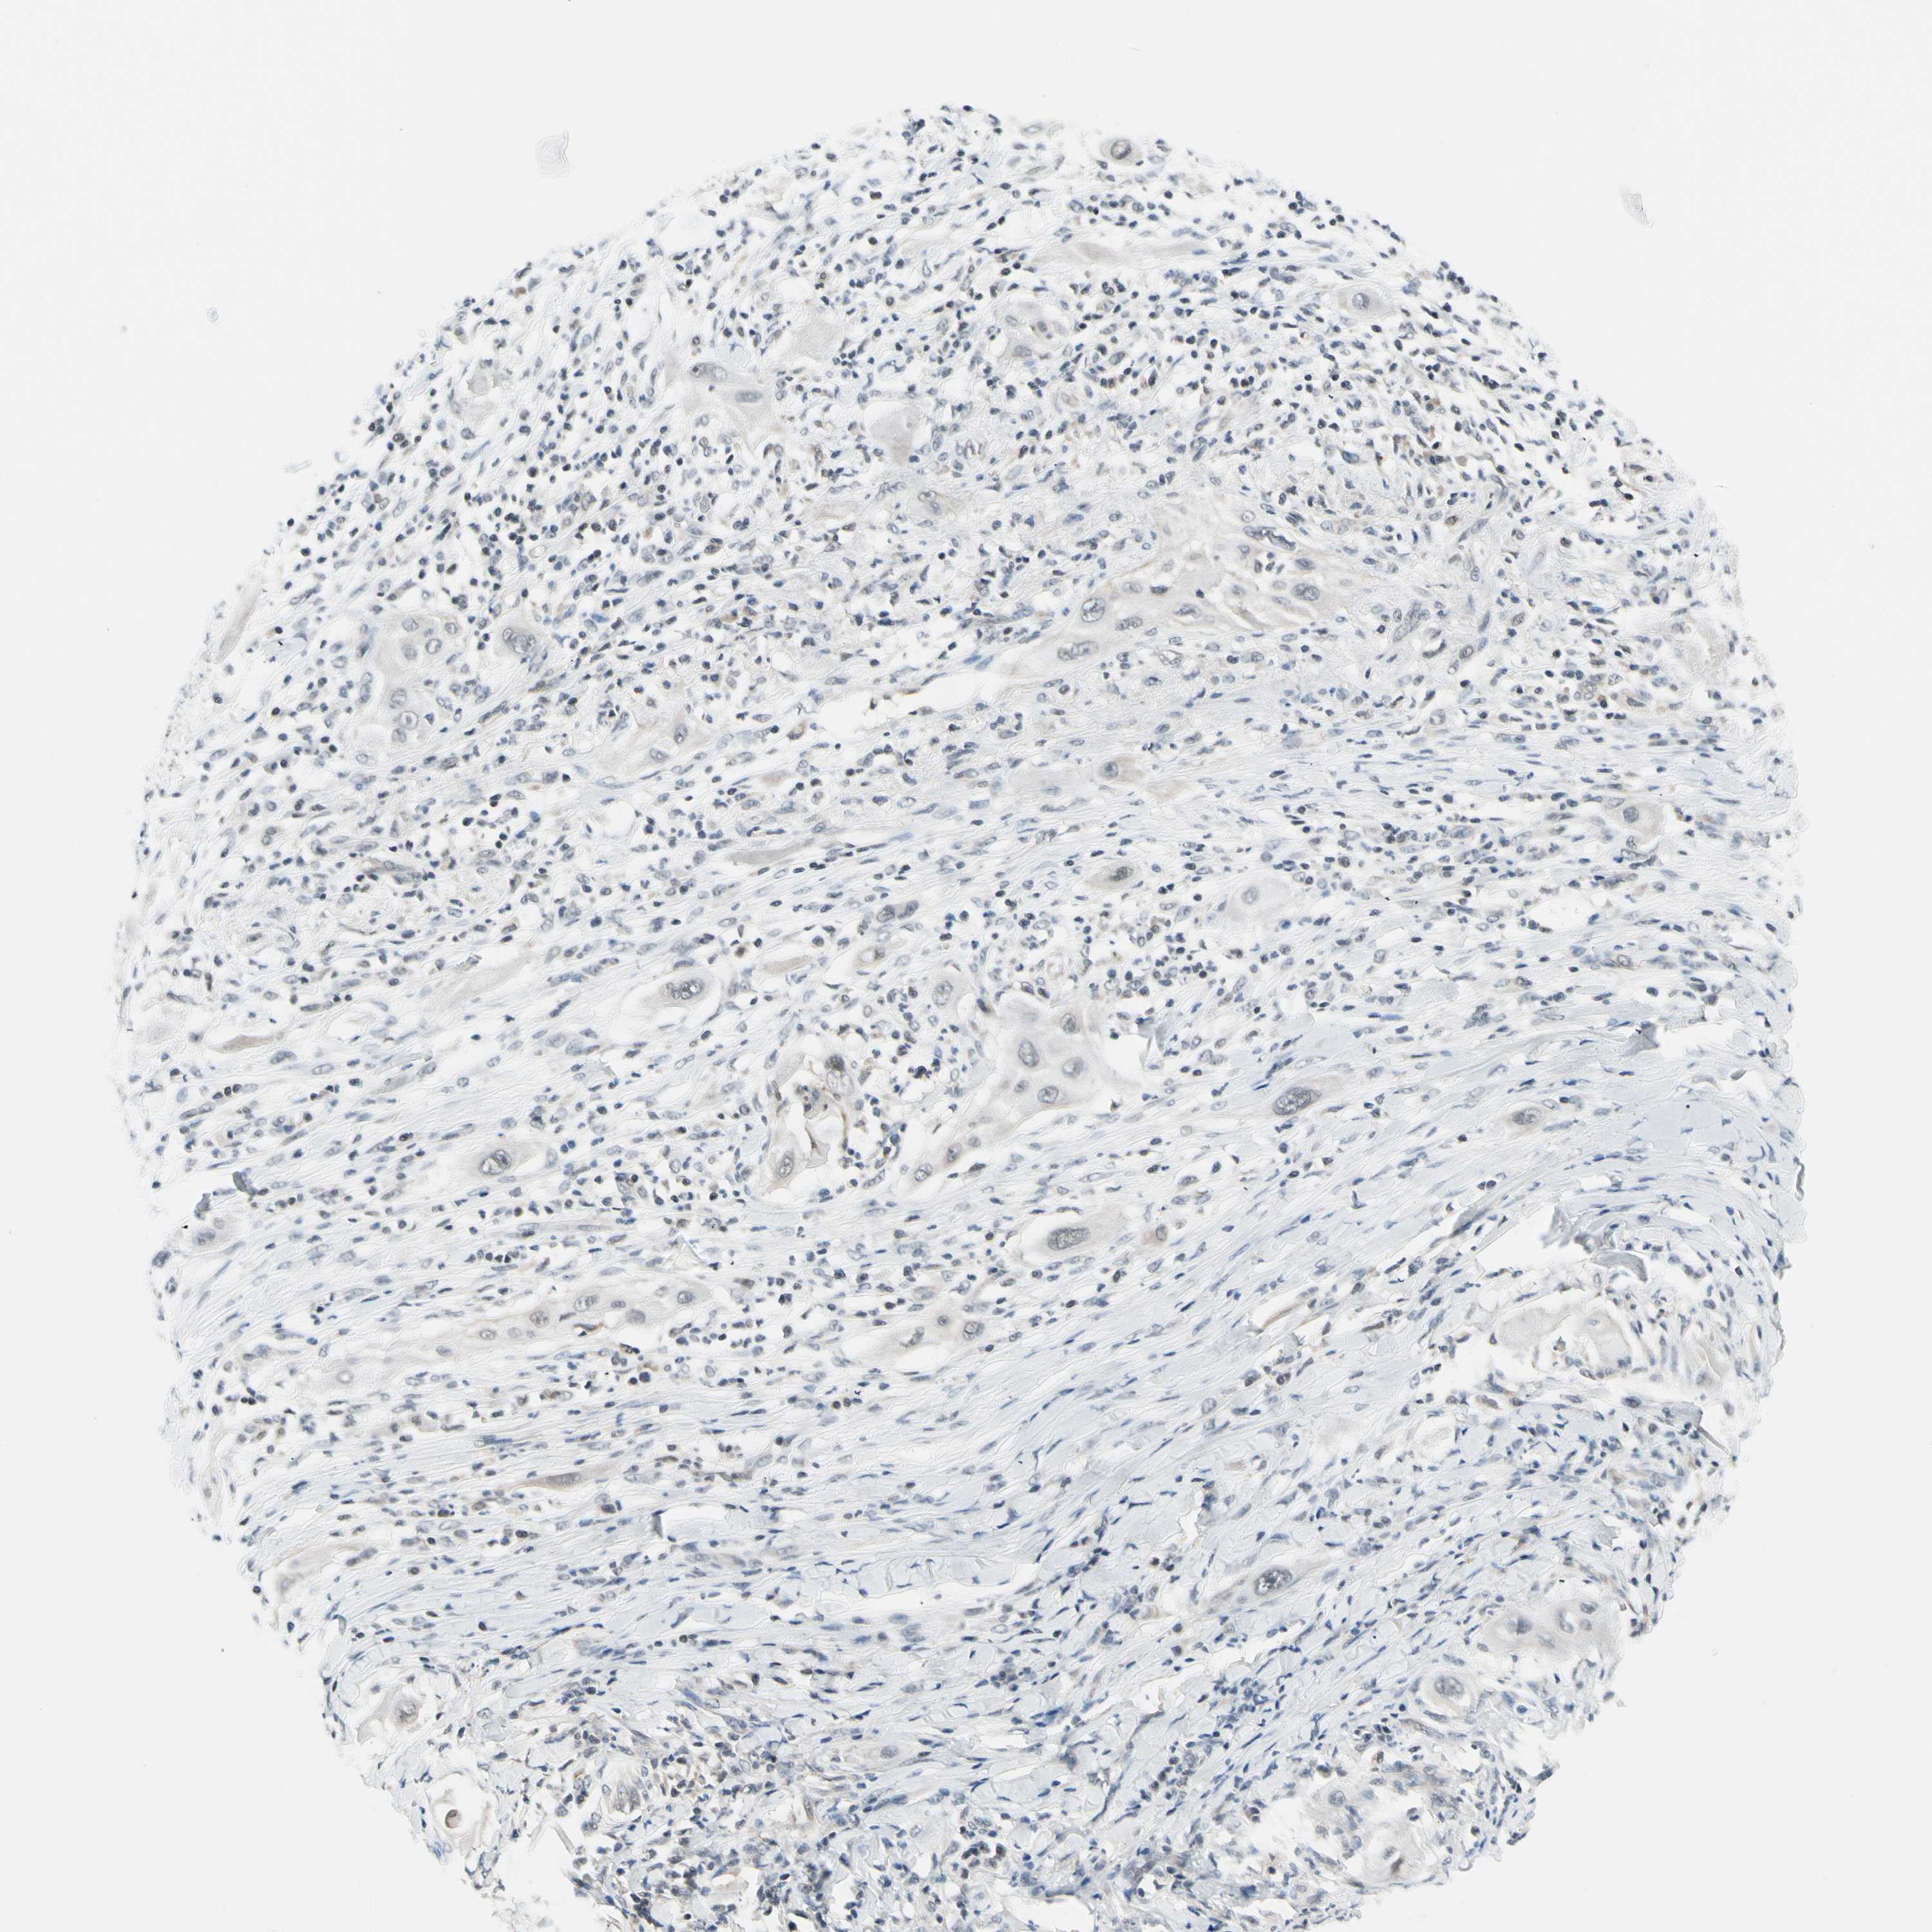

TAF12